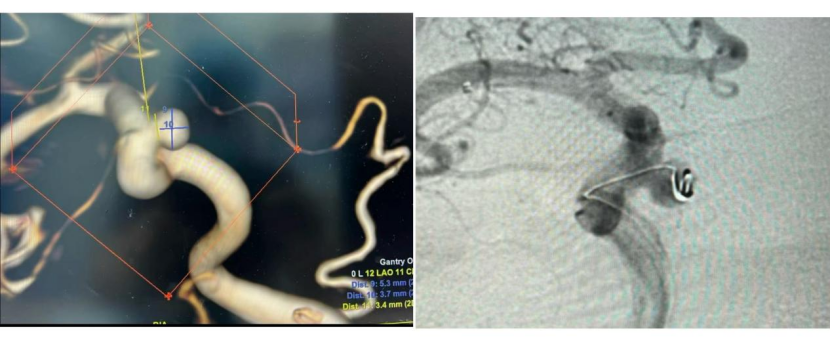

该患者因突发口角歪斜前往济南南郊医院就诊,本以为仅是轻微脑梗塞问题,但经过详细的颅脑磁共振(MRA)检查后,发现患者患有“颅内不定时炸弹”——颅内动脉瘤。影像结果显示,在患者颈内动脉C6段(眼动脉段)存在一个大小为5.3*3.9mm的动脉瘤。脑科主任郭晓宾主任分析指出,此动脉瘤不仅瘤颈宽达3.0mm,属于处理难度较大的“宽颈动脉瘤”,且其最大直径已超过5mm的临床预警线,意味着存在不可忽视的破裂出血风险,必须尽早干预。

面对这一情况,郭晓宾主任团队与患者家属进行了全面、深入的沟通。基于动脉瘤的形态和位置,团队提供了两种主流的微创介入治疗方案:一是植入新型的血流导向装置(密网支架),二是行支架辅助弹簧圈栓塞术。在郭主任详细解释了两种技术的原理、优势及适应症后,家属经过审慎权衡,最终选择了技术成熟、性价比高的支架辅助弹簧圈栓塞术。

手术过程顺利,术后造影证实动脉瘤栓塞致密,载瘤动脉通畅无阻。